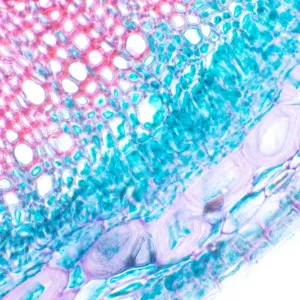

MAGUS Bio 230T – биологический тринокулярный микроскоп для лабораторных и исследовательских наблюдений в медицине, фармацевтике, криминалистике, биотехнологии и других областях науки. Применяется для работы с плоскими полупрозрачными и прозрачными образцами биологического происхождения: тонкими срезами и мазками. Оснащен ахроматической оптикой и галогенной подсветкой, наблюдения ведутся в проходящем свете в светлом поле. Микроскоп рассчитан на установку дополнительных аксессуаров для использования большего количества методов наблюдений: темного поля, фазового контраста, поляризованного света.